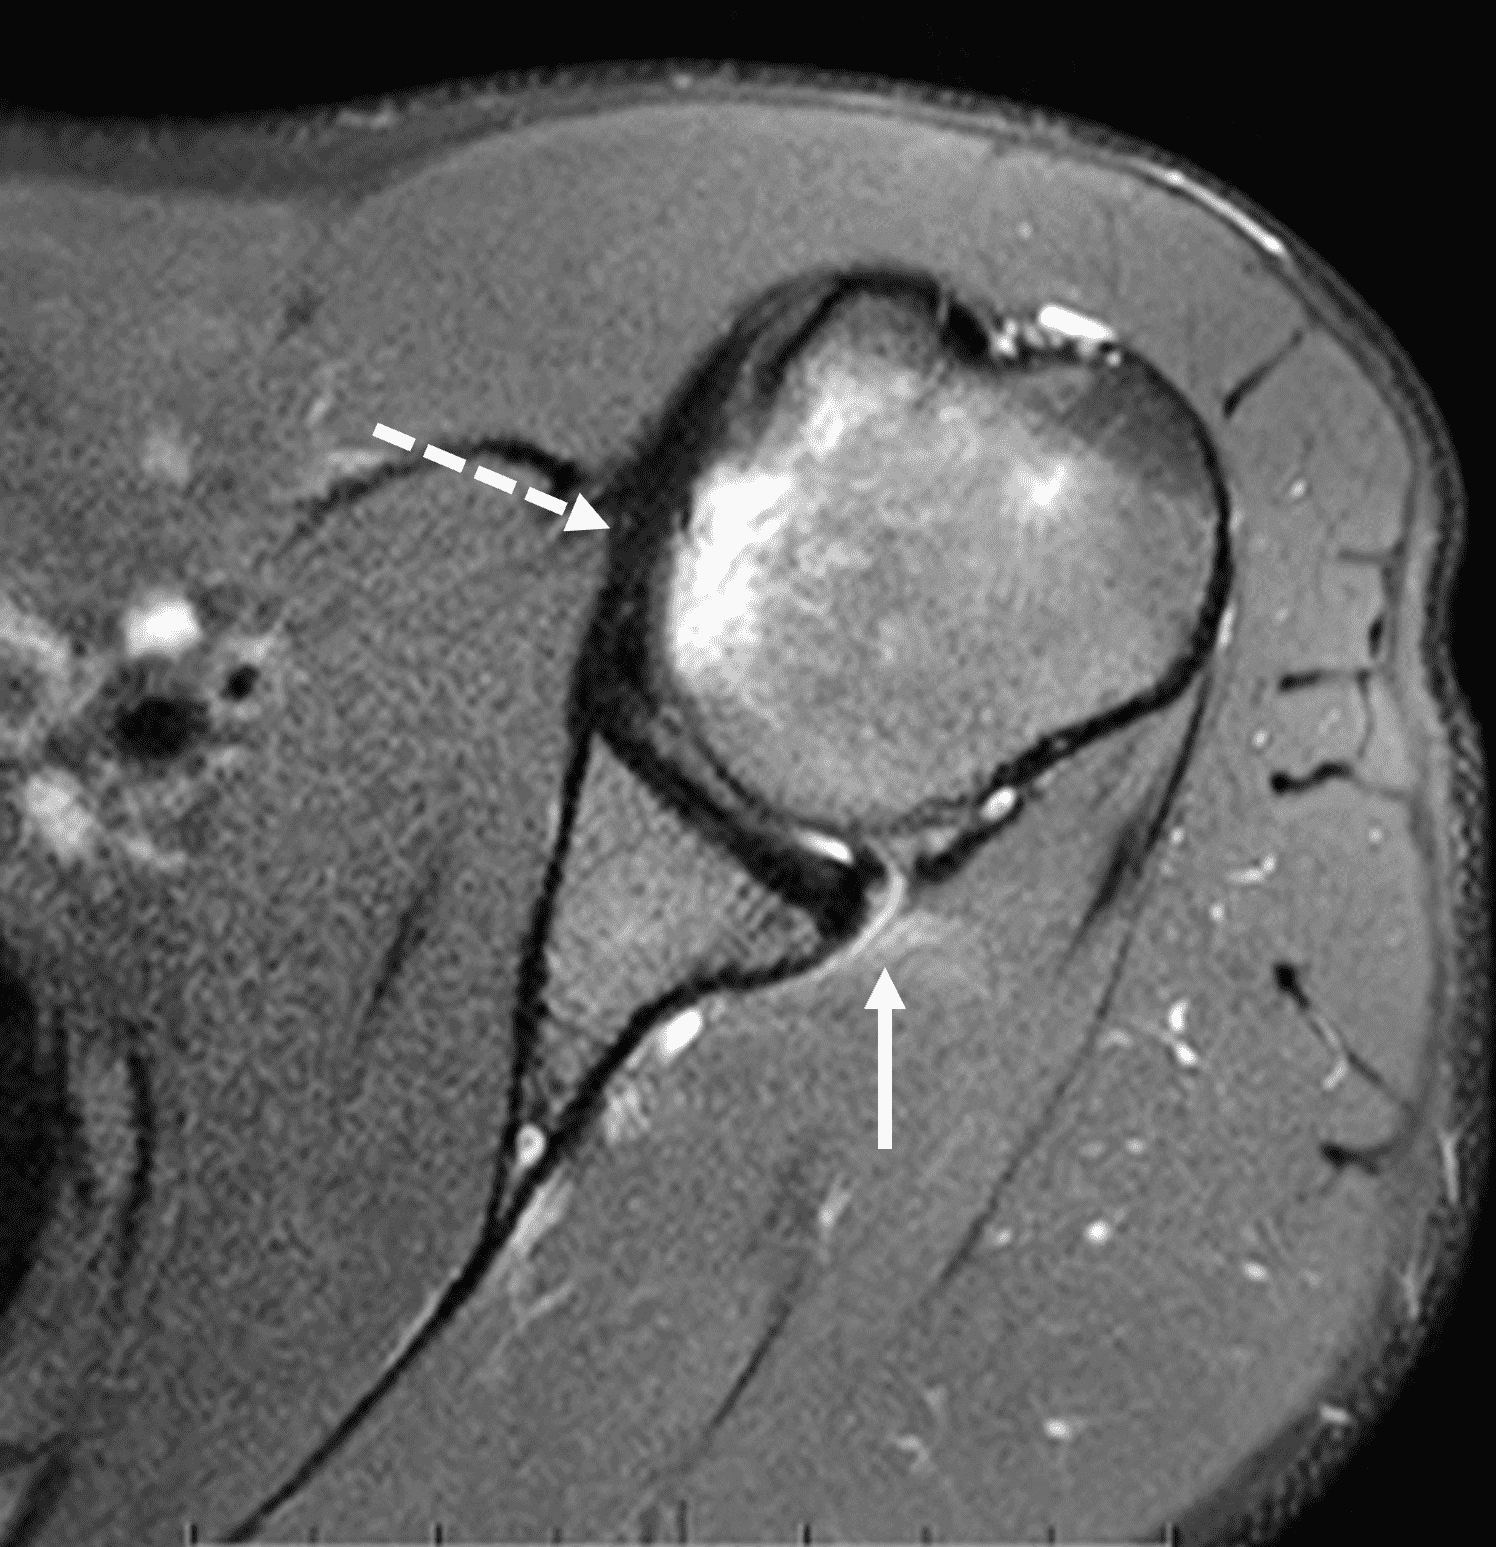

20 year old right-handed hitting college baseball player with left shoulder injury. Fat-suppressed proton-density-weighted axial images at the mid (1A) and inferior (1B) left glenohumeral joint are provided. What are the findings? What is your diagnosis?

Figure 2: The axial images (2A and 2B) demonstrate findings of a posterior glenohumeral instability injury including posterior to posteroinferior capsulolabral tearing and pericapsular edema (solid arrows) and an anteromedial humeral head impaction injury (dashed arrows).